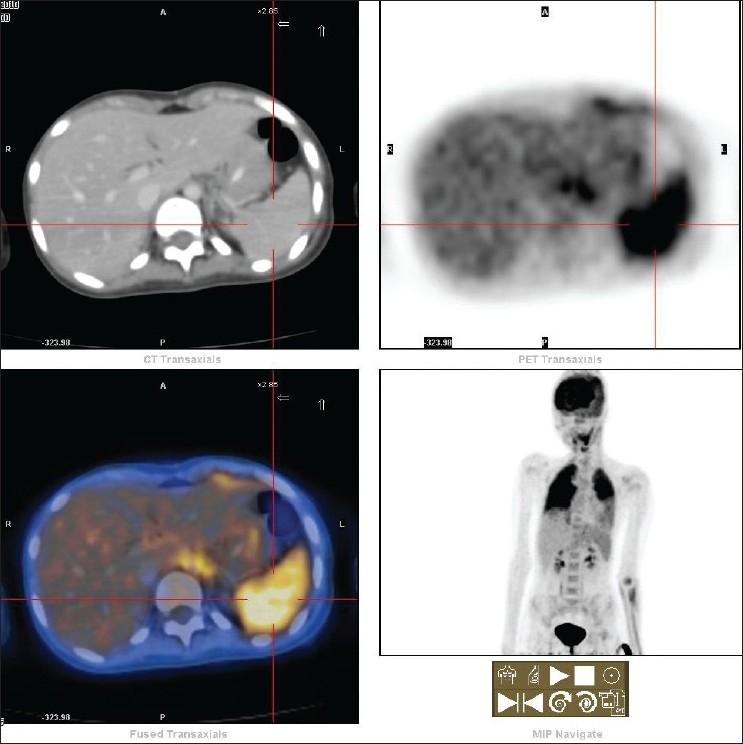

Anti N-methyl-D-aspartate receptor encephalitis (ANMDARE), also known as limbic encephalitis (LE), is a treatable rare disorder characterized by personality changes, irritability, depression, seizures, memory loss and sometimes dementia. It is classified under paraneoplastic syndrome (PNS) and produces antibodies against NR1 and NR2 subunits of glutamate aspartate receptor. It is thought to be closely related with malignancies like small cell lung cancer, ovarian teratoma and Hodgkin's lymphoma, apart from testis, breast and rarely gastric malignancies. Non-paraneoplastic encephalitis cases are the ones with no detectable malignancy and may be triggered by severe infection. As nuclear medicine physicians, we must be aware of the diverse presentation of ANMDARE or LE and should include a whole body positron emission tomography / computed tomography (PET/CT) and not just brain PETCT during imaging. We describe the first case of PET/CT in an idiopathic ANMDARE Indian adolescent girl.

抗N-甲基-D-天冬氨酸受体脑炎(ANMDARE),也称为边缘叶脑炎(LE),是一种可治疗的罕见疾病,其特征包括人格改变、易怒、抑郁、癫痫发作、记忆丧失,有时还会出现痴呆。它被归类为副肿瘤综合征(PNS),并产生针对谷氨酸天冬氨酸受体NR1和NR2亚基的抗体。除了睾丸、乳腺以及很少见的胃恶性肿瘤外,它被认为与小细胞肺癌、卵巢畸胎瘤和霍奇金淋巴瘤等恶性肿瘤密切相关。非副肿瘤性脑炎病例是指未检测到恶性肿瘤的病例,可能由严重感染引发。作为核医学医生,我们必须了解ANMDARE或LE的多样表现,并且在成像时应进行全身正电子发射断层扫描/计算机断层扫描(PET/CT),而不仅仅是脑部PETCT。我们描述了一名患有特发性ANMDARE的印度青春期女孩的首例PET/CT病例。